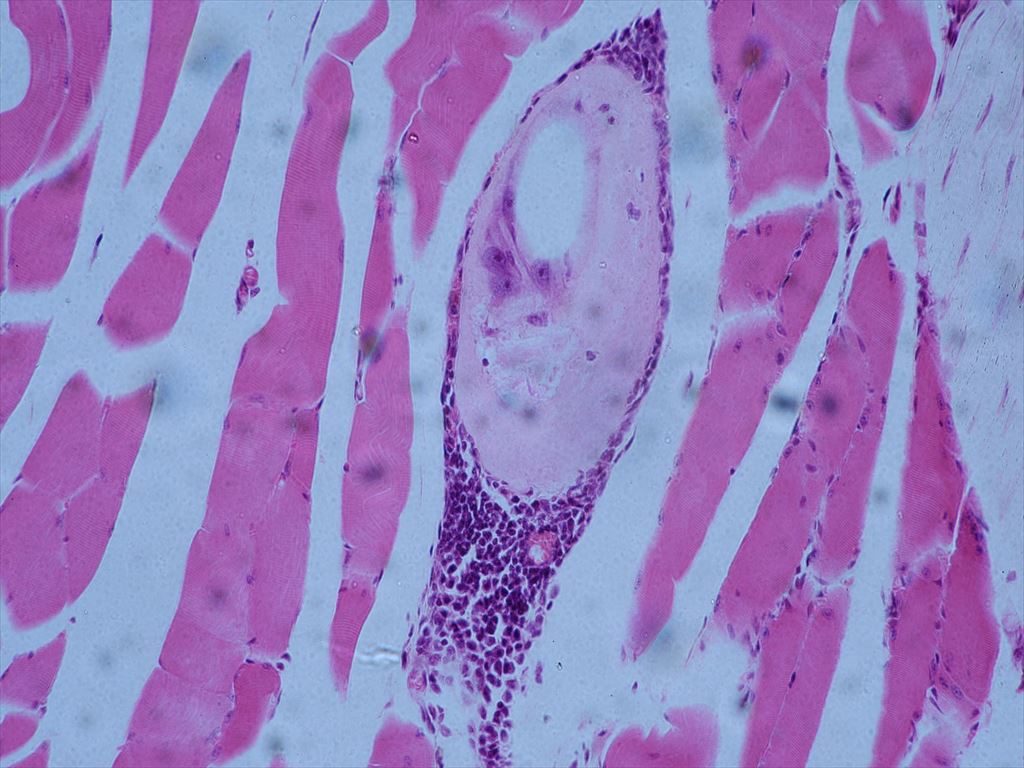

036-Trichinella larvae cysts sec.(HE)【トリヒナ症・旋毛虫(センモウチュウ)幼虫・シスト(眠時期) (切片)(HE染色)】【寄生虫・プレパラート標本】

※機械翻訳の為日本語は寄生虫学用語と異なる場合が有ります、また撮影措置の解像度が低く不鮮明な場合があります

※医学知識に乏しくタイトルと合わない場所を撮影してる場合があります

094-Trichinella spiralis muscle sec.【トリヒナ症・旋毛虫(センモウチュウ)筋(切片)】【寄生虫・プレパラート標本】